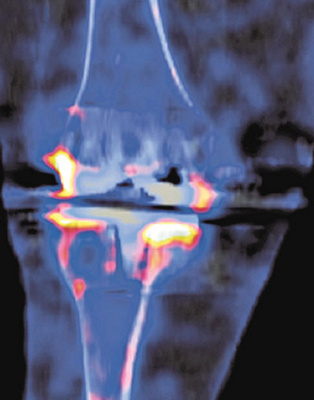

Abb. 3

Postoperatives Röntgenbild mit der geführten Knieprothese. Die Gelenklinie wurde verbessert und durch die Führung wurde das Gelenk stabilisiert.

Am Tag der Operation durfte sie in Begleitung der Physiotherapie das erste Mal aufstehen. Nach wenigen Tagen war sie bereits selbständig an Stöcken mobil und schon nach fünf Tagen verliess die Patientin das Spital zur weiteren Rehabilitation. In der Kontrolle sechs Wochen nach der Operation (Abb. 3) erschien Andrea Ohnsorg ohne Stöcke. Und sie war auch schon wieder in ihrem geliebten Garten.